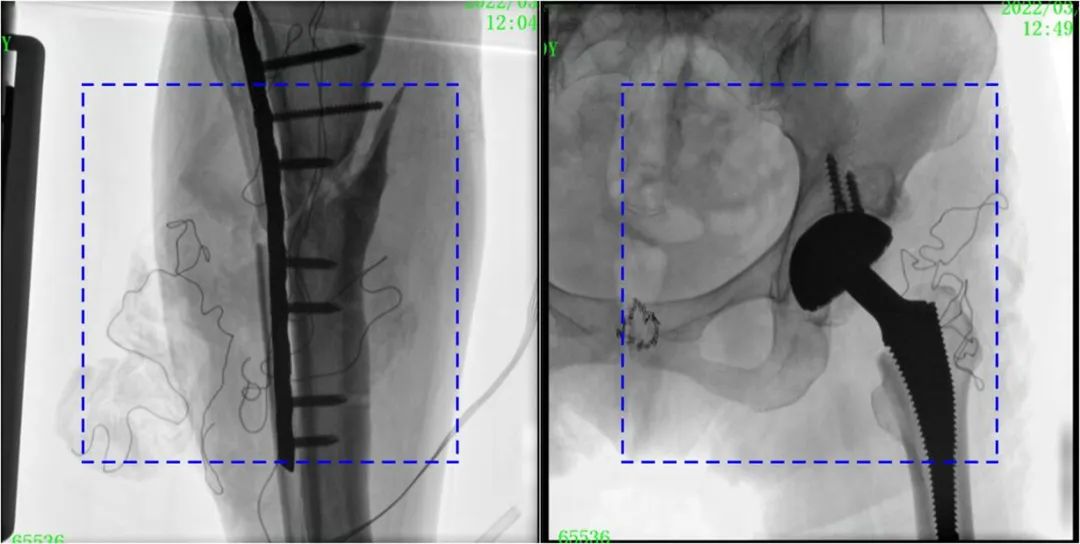

PLX119C臨床圖像與傳統(tǒng)圖像對比

注:藍色虛線內(nèi)為傳統(tǒng)21CM×21CM平板的成像區(qū)域。